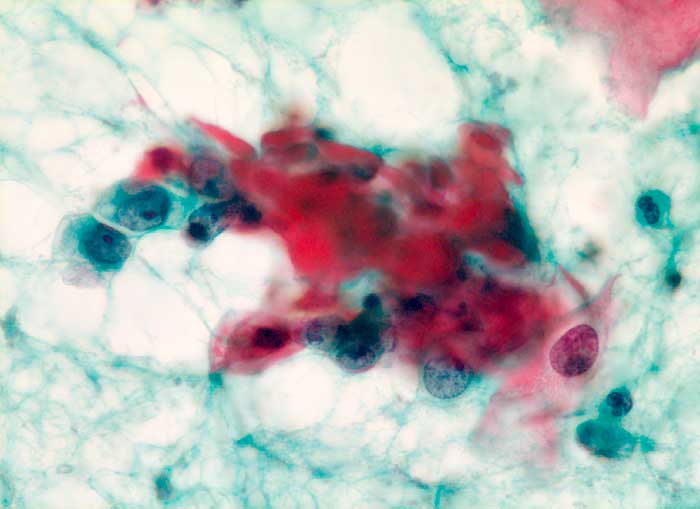

Die Tumorzellen liegen einzeln oder in kleinen Verbänden und ganzen Gewebsfragmenten. Die polymorphen Kerne sind vergrössert und enthalten verklumptes unregelmässig verteiltes Chromatin und grosse Nukleolen. Gut differenzierte Karzinome erkennt man am breiten und oft verhornten Zytoplasma. Längliche bis fadenförmige Tumorzellen mit pyknotischen Kernen können als einziger Hinweis auf das Vorliegen eines Karzinoms vorhanden sein. Wenig differenzierte Karzinome haben polymorphe und schlechter erhaltene Kerne. Der Hintergrund ist meist detritisch und oft hämorrhagisch. Ulzeration, Einblutungen und bakterielle Infektionen beeinflussen den Erhaltungszustand und die Art der abgestrichenen Zellen. Ist die Oberfläche eines ulzerierten Karzinoms von einem Fibrinschorf bedeckt, enthalten die Ausstriche lediglich Detritus, Granulozyten und Erythrozyten, aber keine Tumorzellen. Die Sensitivität für die Karzinomdiagnose ist aus diesem Grund geringer als für die Diagnose eines Carcinoma in situ.

Unten werden drei Fallbeispiele mit histologischer Korrelation gezeigt.